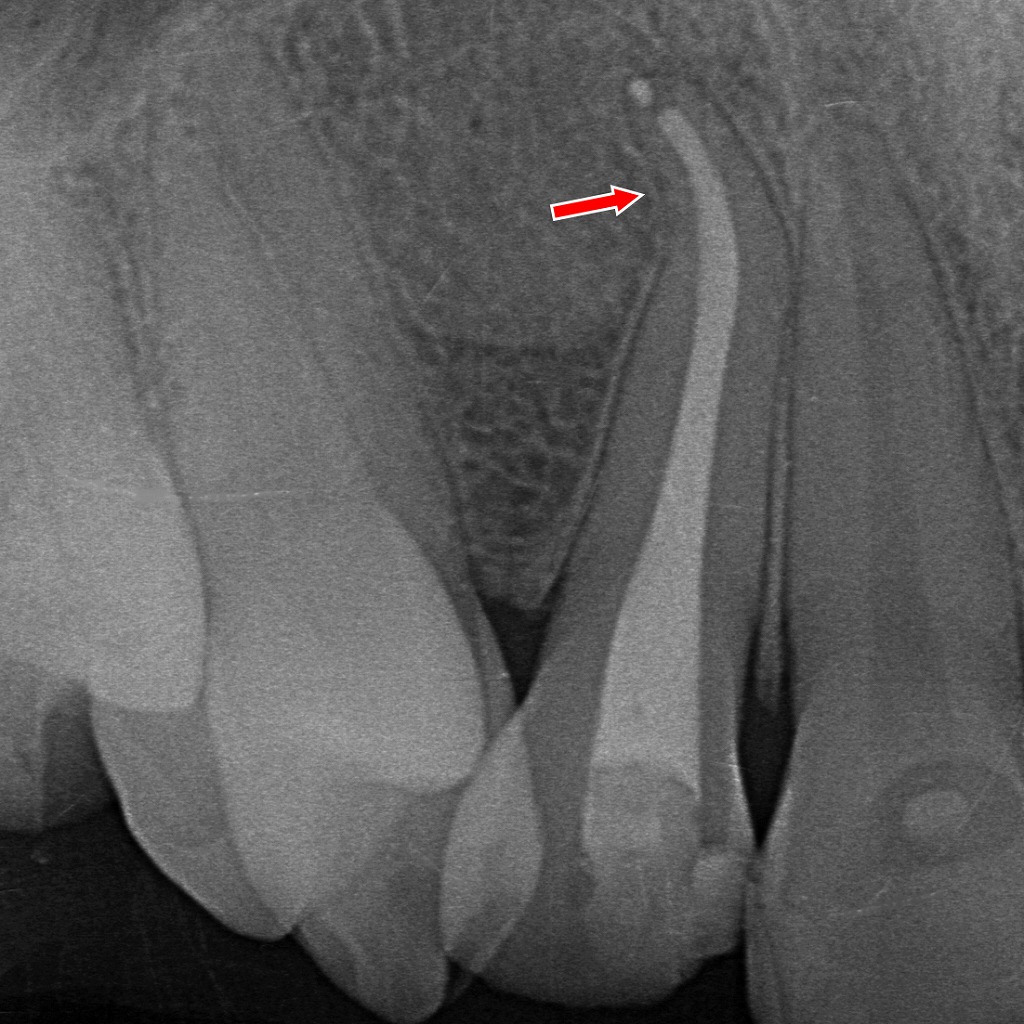

下顎大臼歯の根充後X線写真を例に

下顎の大臼歯は、歯の中でも最も根管治療が難しい部位といわれます。その理由は、根管の構造が非常に複雑で、器具操作が難しいためです。下記のポイントが、治療が長期化する主な要因となります。

1. 根管が大きく湾曲している

下顎大臼歯の遠心根・近心根は、しばしば大きくカーブしています。

添付のレントゲン写真でも、根尖付近で根管が大きく弯曲している様子が確認できます(赤矢印部分)。

この湾曲があることで

- 器具が根の形に沿って進みにくい

- 器具が破折するリスクが上がる

- 洗浄・拡大が不十分になりやすい

といった問題が生じ、治療時間がどうしても長くなります。

③ 垂直加圧充填(垂直根充)

ガッタパーチャを加圧して側枝の方向にまで緊密に封鎖できるため、

側枝感染の再発防止に有効です。

ガッタパーチャを垂直方向に加圧して柔らかくし、主根管だけでなく側枝の先端まで緊密に封鎖する“垂直加圧充填”の症例。赤矢印は側枝方向まで充填材が行き渡っている状態を示しています。複雑な側枝形態でも細菌の侵入を防ぎ、治療後の再感染リスクを大幅に下げることができます。